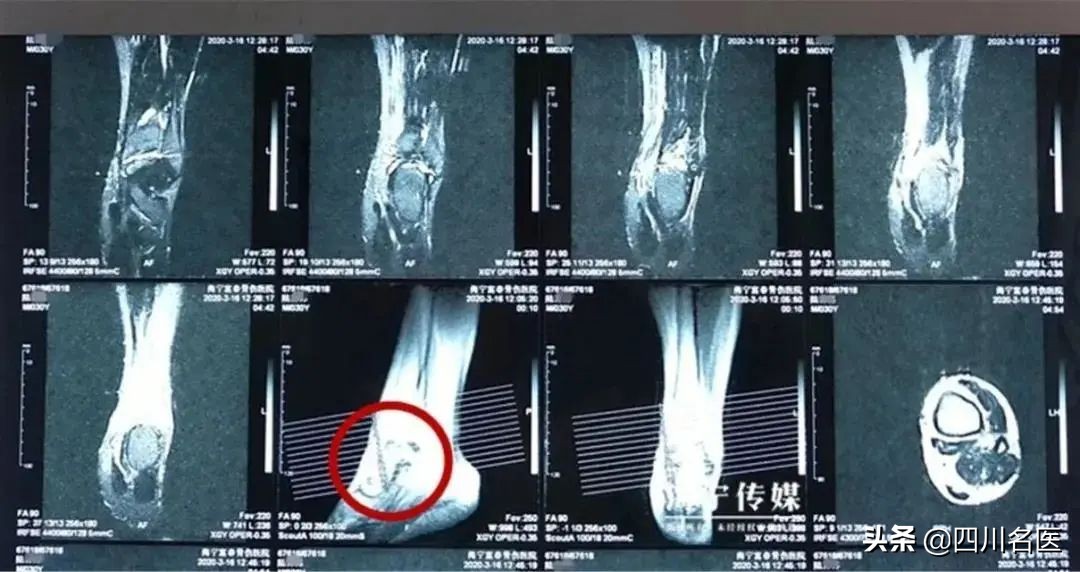

检查显示,陆先生左踝距腓骨前韧带距骨止点撕裂等多处韧带撕裂,还伴有大量积液。这样严重的症状,到底是怎么导致的呢?

△脚踝处有大量积液(图片来源:见水印)